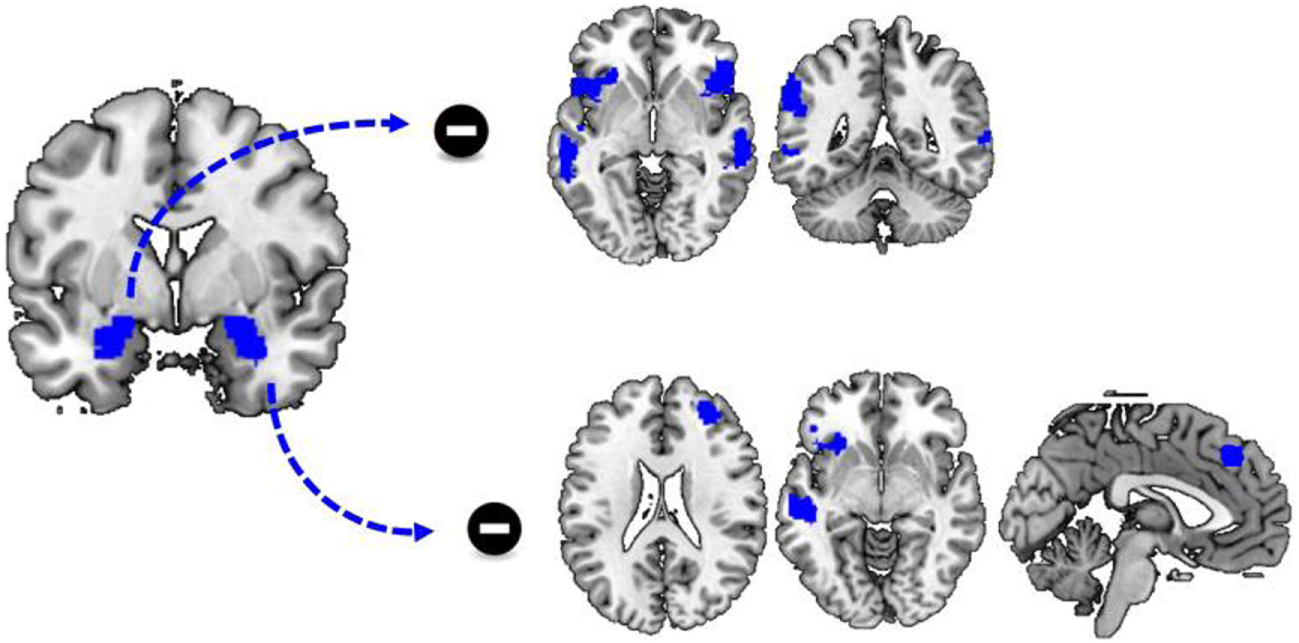

FIGURE 3

www.frontiersin.org

Figure 3. Childhood trauma and functional connectivity. There was a significant group by childhood trauma interaction on functional connectivity between the left amygdala and the dorsal striatum. While childhood trauma was negatively correlated with functional connectivity between the left amygdala and bilateral dorsal striatum in non-drug using controls, childhood trauma was positively correlated with functional connectivity between the left amygdala and left middle frontal cortex and right dorsal striatum.

The Relation between Functional Connectivity and State Anxiety

For both the left and right amygdala as seed region, there was no significant group by stimulus type by state anxiety interaction effect. however, there was, a negative correlation between state anxiety and functional connectivity of the left amygdala to a variety of brain regions during cocaine cue reactivity Figure 4, Table 4. These regions included the bilateral dorsal medial frontal cortex, the left inferior frontal cortex, and the left inferior and middle temporal cortex. No such effects were evident for functional connectivity with the right amygdala as a seed region (Table 4; Figure 3).

Figure 4. State anxiety and functional connectivity. There was a significant negative correlation between state anxiety and functional connectivity between the left amygdala and a variety of brain regions including the dorsal and ventral medial prefrontal cortex.